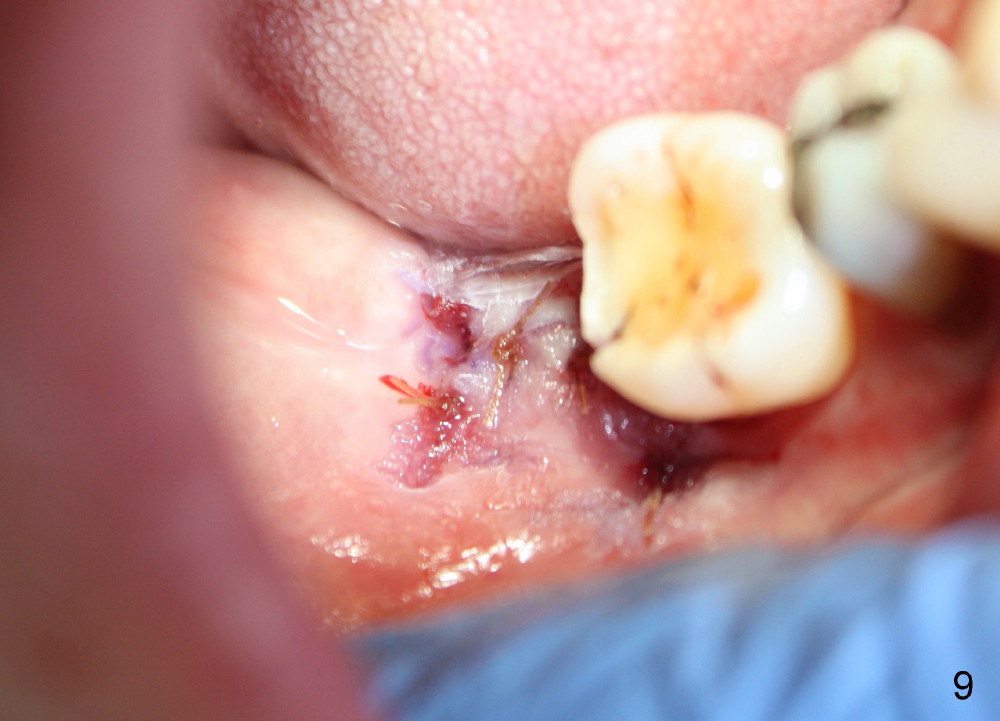

A 57-year-old lady returns for #31 implantation. The vertical edentulous space is limited, as the opposing tooth is supraerupted (Fig.1 arrow). Preop PA is critical (Fig.2), since it is used to measure the bone height (Fig.3: 12 mm). The length of the implant is expected to be 10 mm. The initial osteotomy depth is 8 mm (Fig.4); it appears that the trajectory should be adjusted. Osteotomy increases following depth and angulation adjustment (Fig.5: 4.5x10 mm drill). The submerged implant (5.3x10 mm) is placed with insertion torque approximately 35 Ncm (Fig.6). The buccal microthreads are exposed (Fig.7); to prepare for bone graft, the buccal plate is decorticated. Following placement of freeze dry mineralized allograft, collagen membrane is fixated by a healing screw (Fig.8). The incision is closed by 4-0 Chromic gut sutures and perio glue (Fig.9).

Bone-level implants offer two options after placement (stages 1 and 2). If the insertion torque is high and there is sufficient vertical edentulous space, a healing abutment is placed (stage 1). No surgery is required for restoration. Otherwise, the implant should be buried, as shown in this case. Two mini-implants are going to be placed to intrude the opposing supraerupted tooth. In fact, the orthodontic intrusion is quite difficult. Finally the intrusion apparatus has to be removed prior to chemotherapy for breast cancer. PAs taken 1 year 3 months (Fig.10) and 1 year 9 months (Fig.11, 6 months post cementation) postop appear to show that there is coronal bone loss. An abutment with short cuff (Fig.11 *) is chosen for final crown (C). Ideally the implant should have been placed deeper (Fig.7) for easy restoration. Pre-op examination and diagnosis are critical.